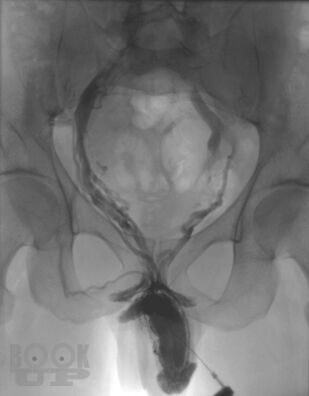

Динамическая кавернозография в диагностике патологии кавернозного бассейна полового члена

В учебном пособии представлены вопросы метода рентгеновского исследования заболеваний кавернозного бассейна полового члена, некоторые анатомо-физиологические аспекты эрекции, показания и противопоказания к проведению динамической кавернозографии, описана методика проведения динамической кавернозографии, а также представлен разработанный авторами алгоритм обследования пациентов с эректильной дисфункцией. Учебное пособие предназначено для врачей рентгенологов и урологов.